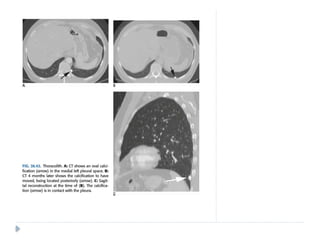

PLEURAL PSEUDOTUMOR

⚫ Is a fluid collection within the lung fissure.

⚫ Most common site : MINOR FISSURE

⚫ Common causes include :

 Congestive heart failure

 Cirrhosis

 Renal insufficiency

⚫ On chest radiographs:

⚫ Classical lenticular or biconvex opacity is seen in

the fissure.

⚫ Usually resolves after therapy with diuretic

agents